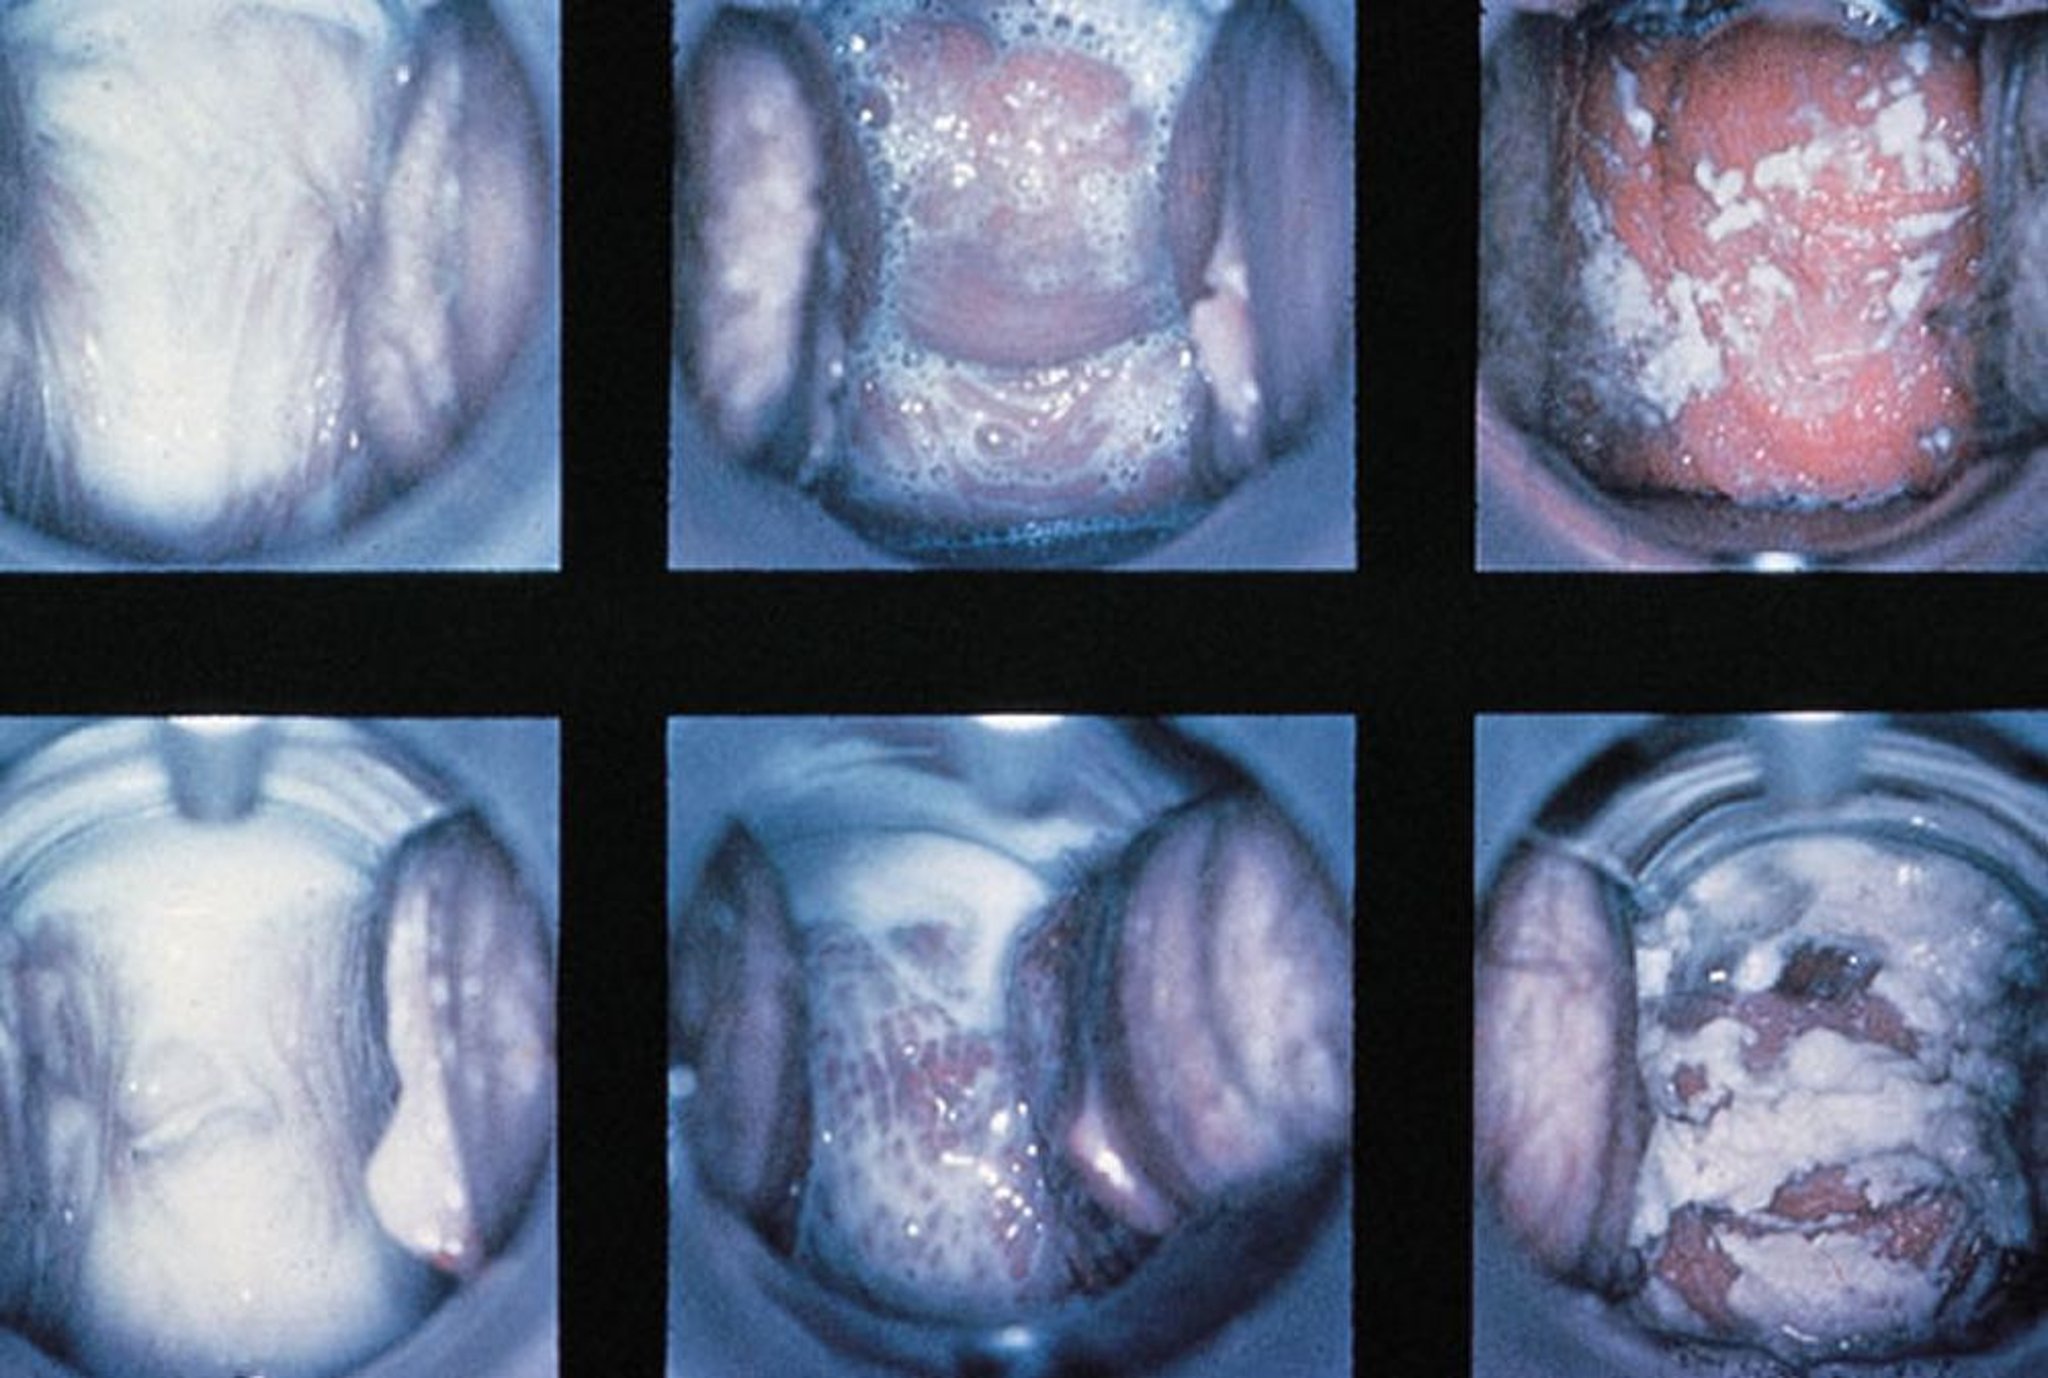

Examen au spéculum dans la vaginite

Des signes normaux, une vaginite à trichomonas avec écoulement mousseux et une vaginite candidosique avec écoulement blanc épais sont montrés (de gauche à droite).

By permission of the publisher. From Spitzer M, Mann M. In Atlas of Clinical Gynecology: Gynecologic Pathology. Edited by M Stenchever (series editor) and B Goff. Philadelphia, Current Medicine, 1998. (Courtesy of the International Society for the Study of Vulvar Disease, from the collection of the late Dr. Herman Gardner.)